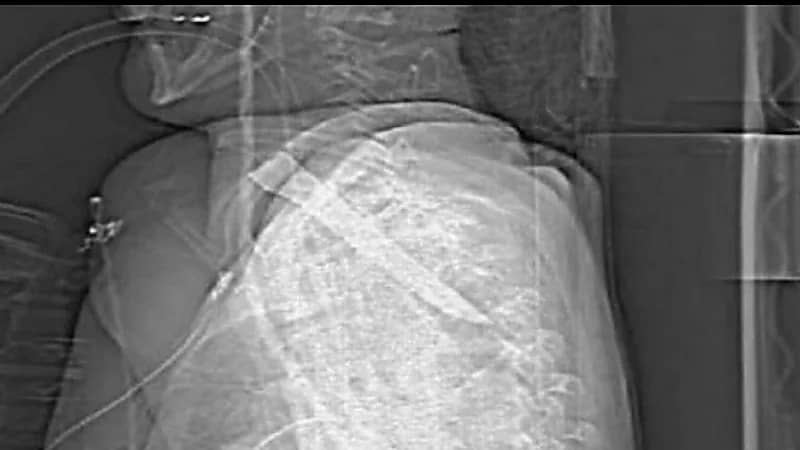

نجا رجل بريطاني من الموت بأعجوبة بعدما تعرض للطعن مما أدى لغرس نصل سكين طولها خمس بوصات ونصف في عنقه، ومن المتوقع أن تكون الطعنة قد تسببت له في إعاقة طويلة الأمد

وقال المدعي العام، للمحكمة، أن الضحية خضع لعملية جراحية طارئة لإزالة نصل السكين بعد الحادث في شيلدون، مقاطعة دورهام.